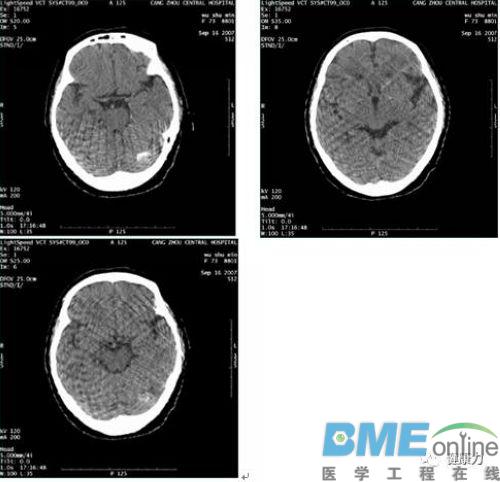

- GE Lightspeed VCT间歇性伪影检修

- 摘要:设备名称:GE CT设备型号:Lightspeed VCT V/R 07MW18.4检测说明:1、 故障现象,扫描间歇性伪影。扫描条件为120KV 200mA 4i,伪影见下图。2、 报错信息如下:解决办法:1、 清